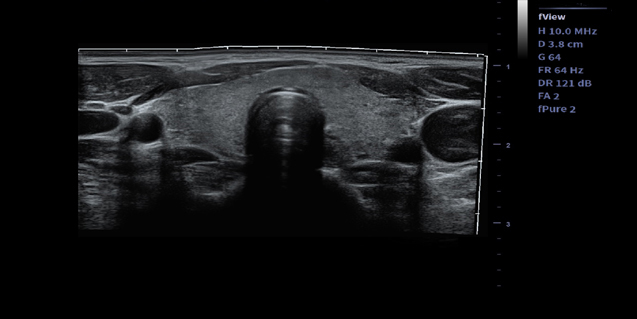

临床图像

线阵探头L12-4

适用于浅表组织、小器官,神经,血管等